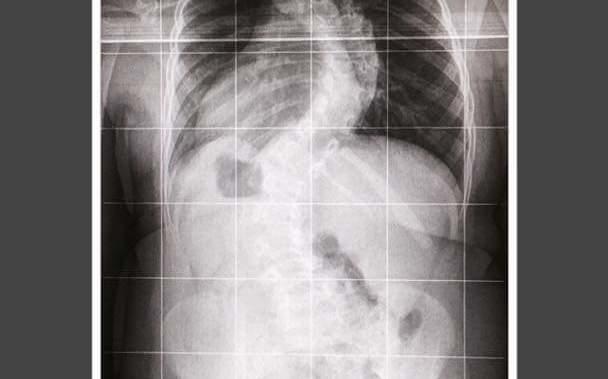

Zależy nam na zdrowiu i bezpeczeństwu pacjentów, którzy muszą zostać poddani operacji kręgosłupa. Doskonałym narzędziem, które wspomaga pracę lekarza jak i zdecydowanie zwiększa bezpieczeństw Pacjenta jest neuromonitoring śródoperacyjny. Elektrody, przypięte do pacjenta, generują i odbierają sygnały, które można odczytać i interpretować na monitorze podczas operacji.

Dzięki neuromonitoringowi możemy też zmnejszyć ilość wykonywania zdjęć RTG i nie narażać Pacjentów na dodatkowe promieniowanie rentgenowskie.